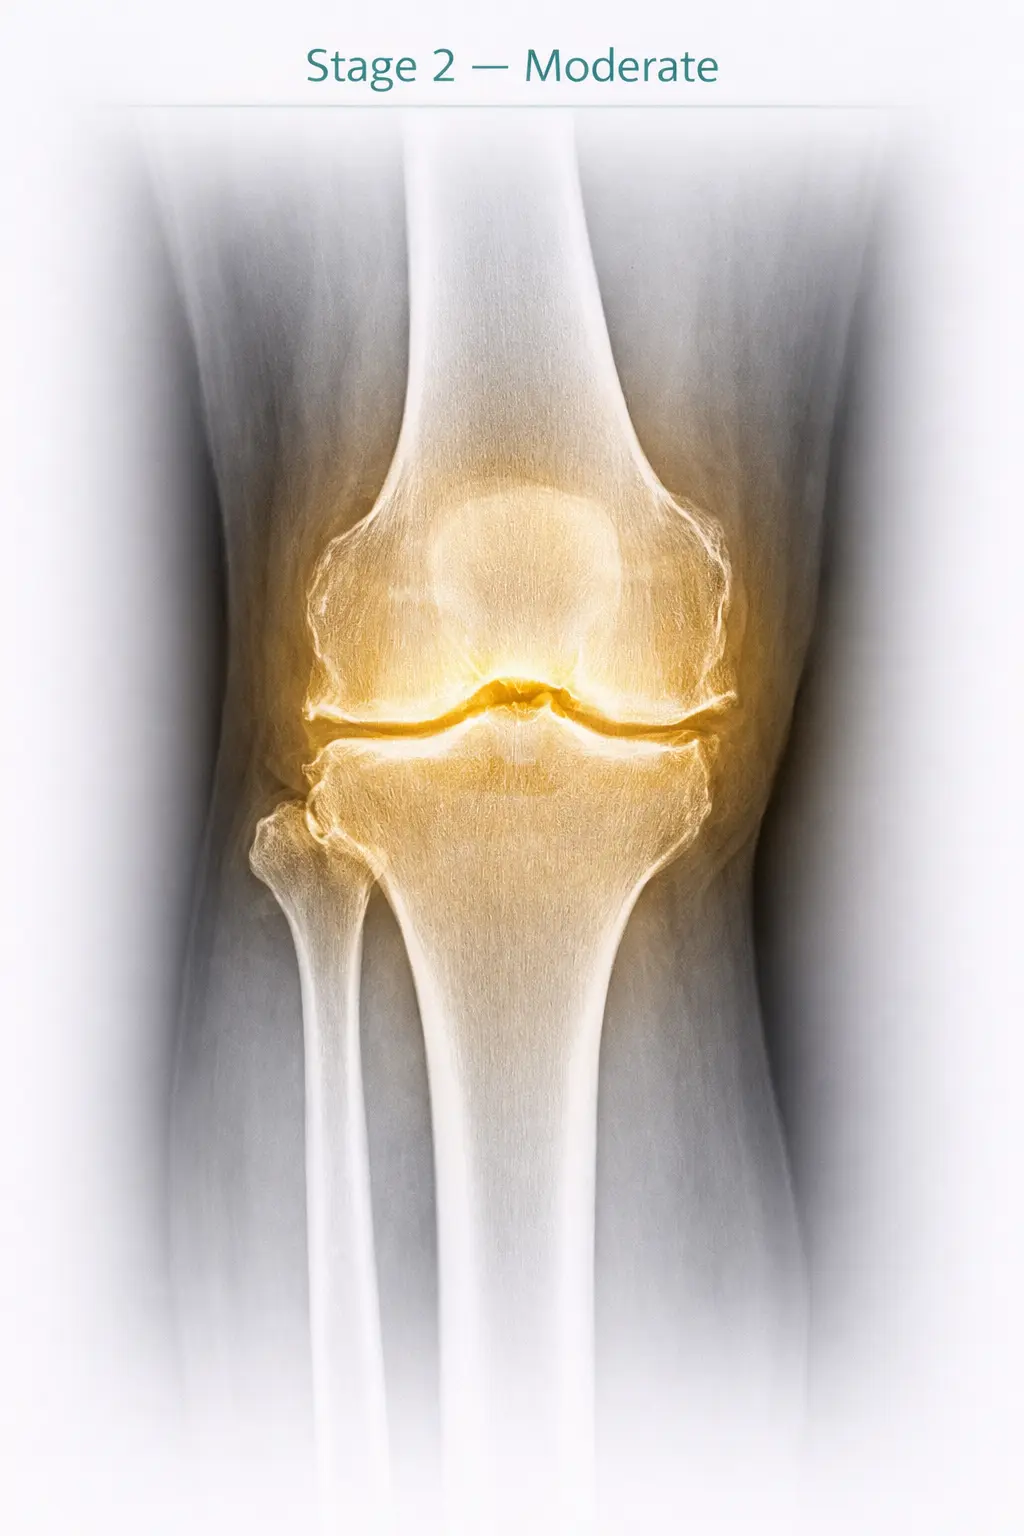

2

Stage 2

Moderate

Symptoms

• Pain increases

• Pain on getting up from sitting position

• Difficulty in long distance walking

X-ray Findings

Decreased joint space medially

Stage 2 - Moderate osteoarthritis in knee joint X-ray